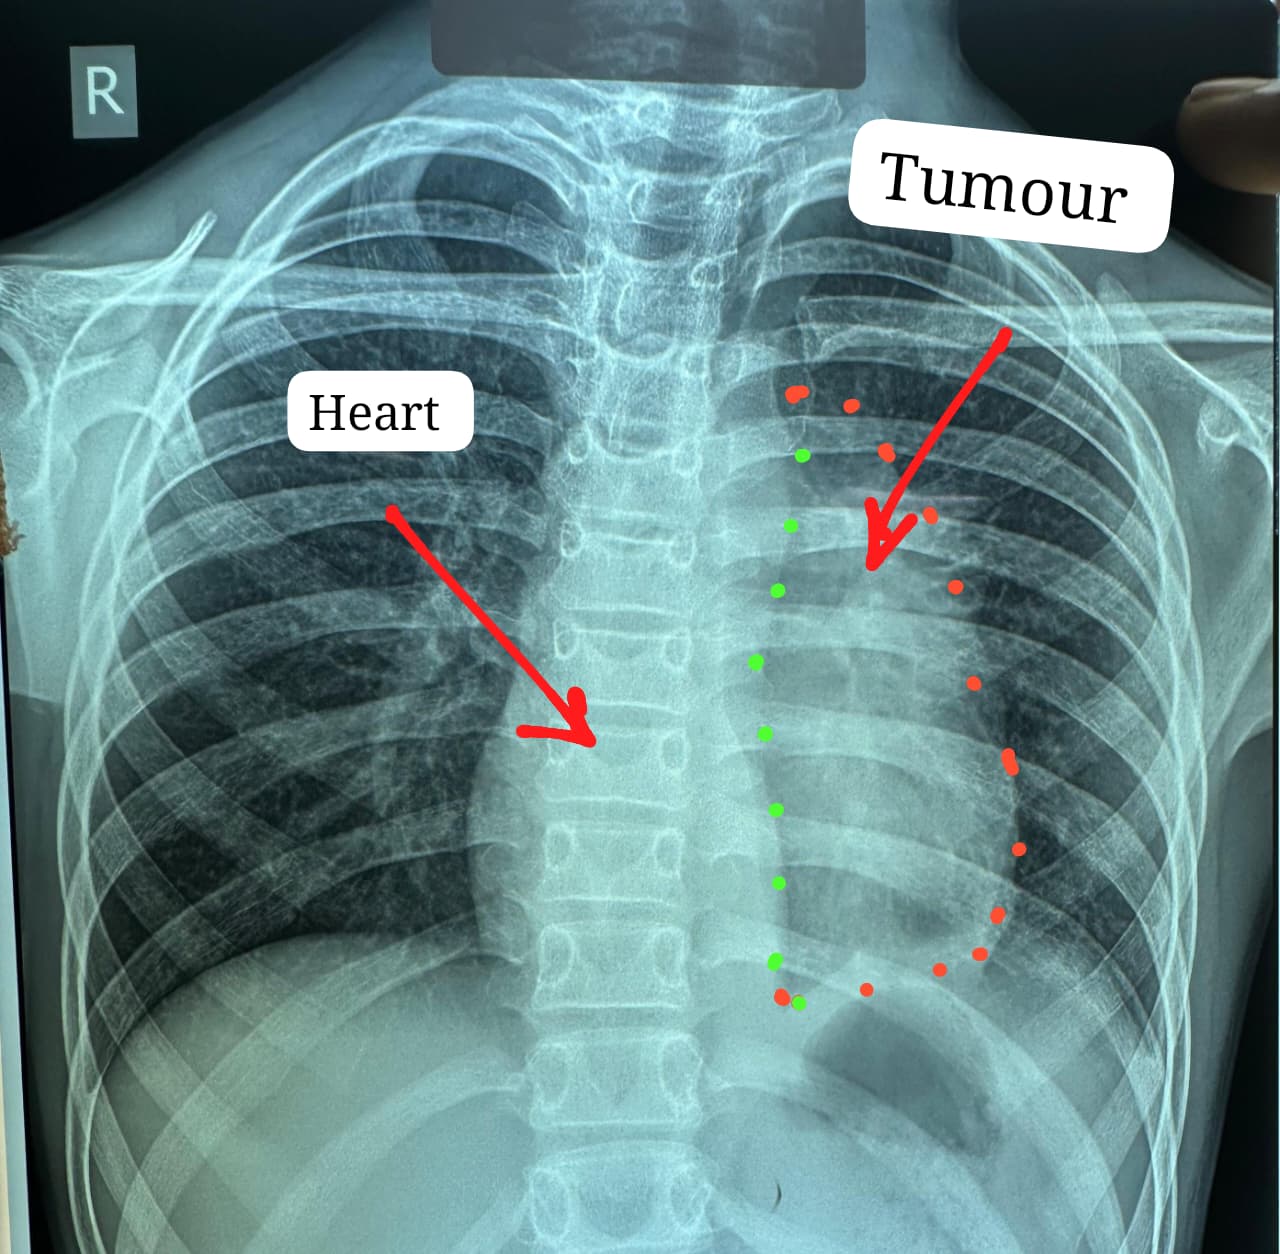

डॉक्टरों के मुताबिक यह ट्यूमर सामान्यतः 40 से 60 वर्ष के लोगों में पाया जाता है और बच्चों में इसका मिलना अत्यंत दुर्लभ है। यह ट्यूमर हृदय, पेरिकार्डियम, फ्रेनिक नर्व महाधमनी (एओर्टा), मुख्य पल्मोनरी आर्टरी, लेफ्ट एट्रियम और फेफड़े से चिपका हुआ था। ऐसे मामलों में ट्यूमर को पूरी तरह निकाल पाना (आर-0 रिसेक्शन) लगभग असंभव माना जाता है, लेकिन अस्पताल में उपलब्ध हार्ट-लंग मशीन की मदद से यह संभव हो पाया।

चांपा निवासी कक्षा छठवीं में पढ़ने वाले इस बच्चे को करीब छह महीने से छाती में दर्द, भारीपन और सांस फूलने की शिकायत थी। जांच में पता चला कि उसके सीने में बड़ा ट्यूमर है, जो हृदय और मुख्य धमनियों से चिपका हुआ है। प्रदेश के कई अस्पतालों में ऑपरेशन से मना किए जाने के बाद मरीज को अम्बेडकर अस्पताल भेजा गया। डॉ. कृष्णकांत साहू ने सीटी स्कैन देखने के बाद परिजनों को बताया कि ऑपरेशन अत्यंत जोखिम भरा है और सर्जरी के दौरान मरीज की जान को खतरा हो सकता है या ऑपरेशन बीच में रोकना पड़ सकता है। इसके बावजूद परिजनों ने सहमति दी और टीम ने सर्जरी का निर्णय लिया।

ऑपरेशन के दौरान किसी भी आपात स्थिति के लिए हार्ट-लंग मशीन तैयार रखी गई थी। लगभग चार घंटे चली सर्जरी के दौरान हार्ट की झिल्ली, फ्रेनिक नर्व तथा फेफड़े के कुछ हिस्से को भी निकालना पड़ा। साथ ही हार्ट के लेफ्ट एट्रियम को भी रिपेयर किया गया क्योंकि ट्यूमर लेफ्ट एट्रियम से चिपका हुआ था। इस दौरान मरीज को चार यूनिट रक्त की आवश्यकता पड़ी।